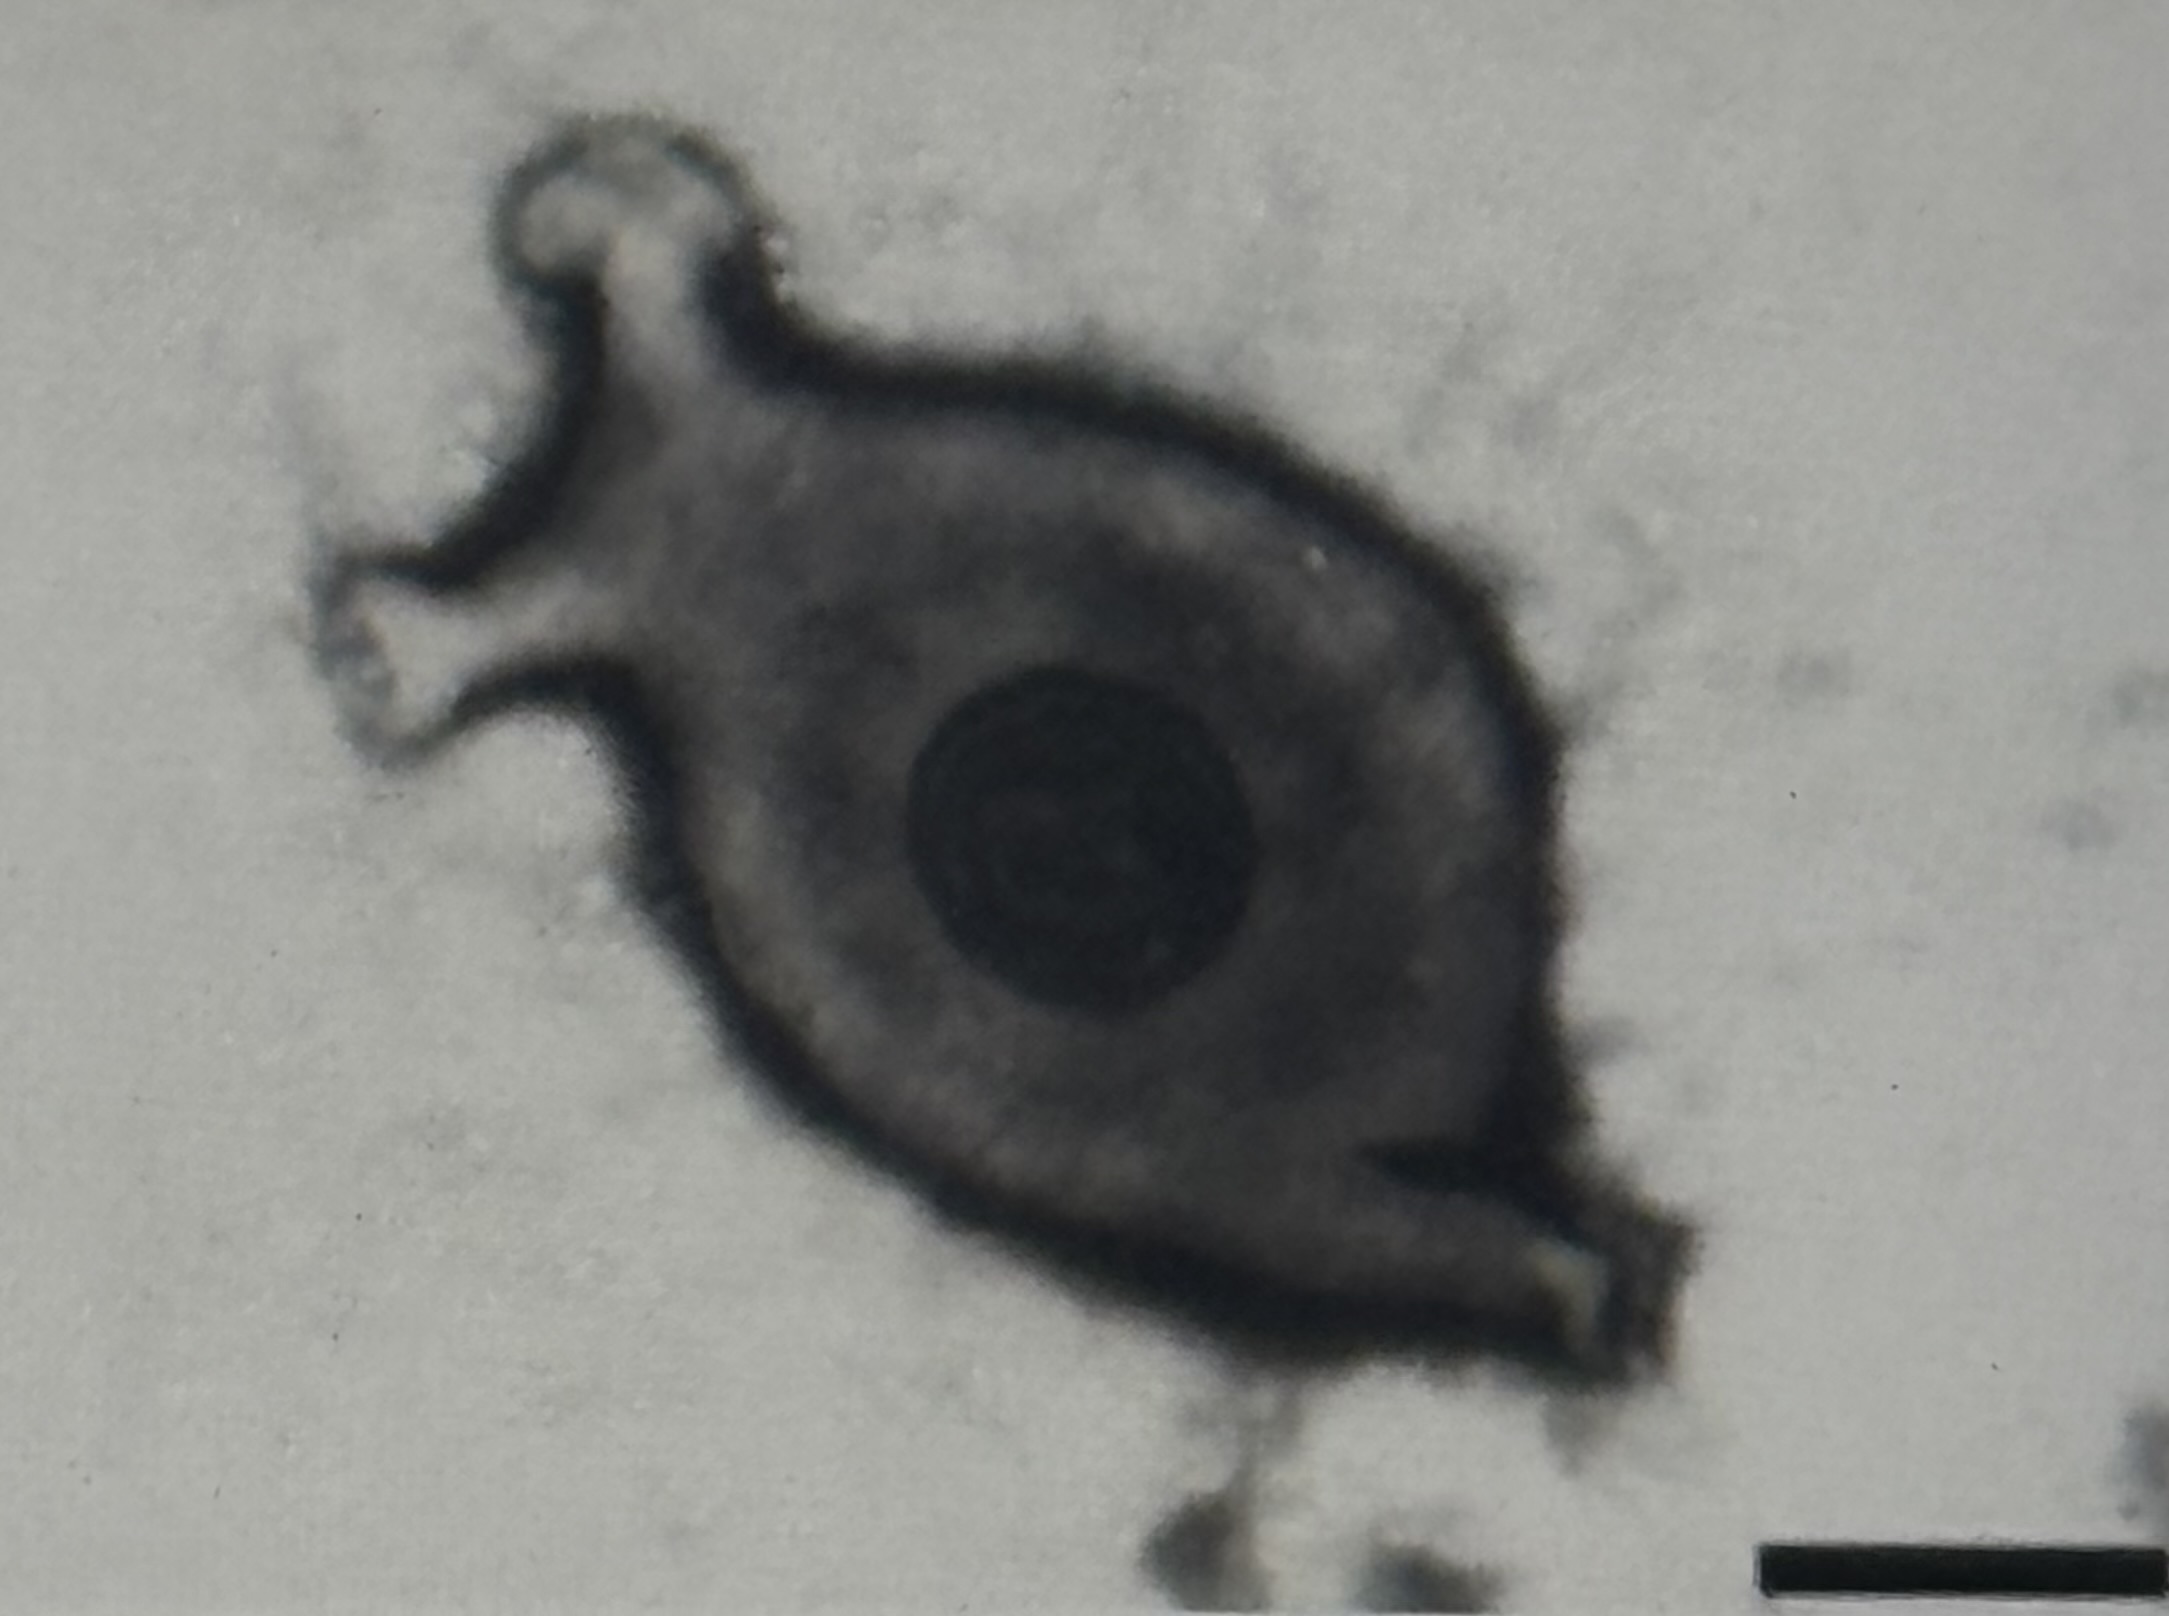

Mycoplasmen Steckbrief

parasitär, teilweise auch kommensalisch, aerob bis fakultativ anaerob

abweichendes Gramverhalten

nur eine Zellwand, kein Peptidoglucan → nicht anfärbbar

vielgestaltig (pleomorph), veränderlich bläschenförmig, 0,2 - 0,3 mikrometer

Pathogenität: parasitär, verursachen chronische Infektionen

z.B. M. pneumoniae (Lungenentzündungen, aber auch Meningitis, Mittelohrentzündung,…) M. hominis (Pyelonephritis, Endometritis und postpartales Fieber)